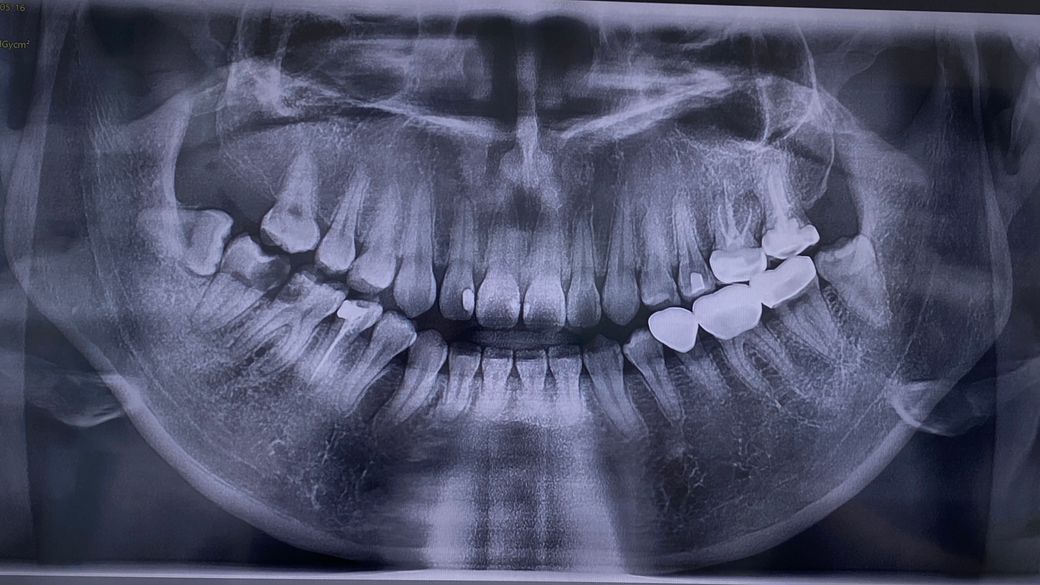

현재 치아 충치 개수? 궁금해요(엑스레이 첨부)

현재 어금니쪽은 충치가 심해서 치료진행중인데 처음에 사진찍었던 엑스레이에요! 까만부분이 충치리고 알고있는데 거의 다 부분적으로 까만부분이 보여서 .. 저 모든 치아가 충치라고 봐야하는건가요...? 치과에서는 치료중인곳 제외하고는 별말씀없으셨는데 다 충치일까봐 얼굴보고는 물어보기가 민망해서 여기에 여쭤봅니디 ㅠ

• 오른쪽 아래 어금니 2개는 심각한 충치가 보여지며, 좌 우측 모두 사랑니는 발치해야 할 것으로 보입니다. 다만 파노라마 사진 상에서는 큰 충치 밖에 보이지 않으며 정확한 진단을 위해서는 임상검사 및 PA 사진 등을 찍어봐야 알 수 있습니다.

오른쪽 아래 어금니 충치로 판단했을 때 대부분의 치아에 미세하게 충치가 있을 가능성이 큽니다.

다수의 충치가 보이고 특히 왼쪽 아래는 충치가 심각한 편입니다.

• 충치의 여부는 엑스레이 사진만으로 확인을 하기 힘듭니다 우측 아래쪽에 있는 치아는 확연하게 충치가 크게 있는 것으로 보입니다 하지만 그 외의 충치는 육안으로도 확인이 필요할 것으로 생각되기 때문에 자세한 확인을 위해서 치과에서 진료를 받아 보는 것을 권유 드립니다

• 안녕하세요 치과의사 김철진입니다. 엑스레이 상으로 까맣다고 무조건충치는 아닙니다. 사진상에 왼쪽 아래는 큰어금니 두개는 치료중이 아니라면 충치가 상당히 진행된 상태인거 같습니다.

1. 왼쪽 아래 6번째 치아, 7번째 치아 깊은 충치 -> 신경치료 가능성 있음, 발치 가능성도 있음

2. 왼쪽 위 두번째 치아 수복물 하방 이차우식 의심

3. 오른쪽 위 네번째 치아 인접면 충치 의심

4. 오른쪽 아래 여덟번째 치아(사랑니) 씹는면 충치 의심

그 외에도 추가적으로 충치가 있을 가능성이 있는 치아 몇개 보이나 이건 해상도가 좀 더 좋은 치근단 방사선 사진(작은 사진)을 찍어봐야 정확히 파악이 가능합니다.